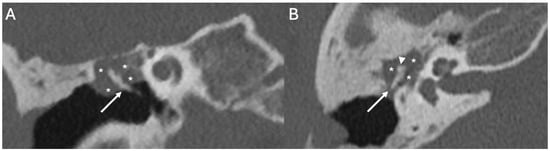

3.3.1. Imaging

3.3.2. Complications

| Cholesteatoma and Otogenic Complications | Kuo et al., 2015 [26]; Baráth et al., 2011 [27]; Mustafa et al., 2014 [28]; Dubey et al., 2010 [29]; Sun et al., 2014 [30]; Lee et al., 2020 [31] | Reviews and retrospective studies | Cholesteatoma causes erosion and CSF leak, leading to meningitis (12–30% incidence); MRI improves detection; pediatric risk emphasized. |